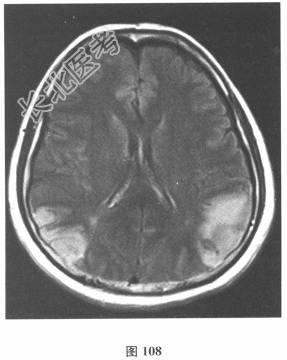

脑脊液检查:常规、生化均正常,CSF-病毒TORCH(-),抗Hu、Yo、Ri均阴性,OB、MBP正常。血清抗Hu、Yo、Ri均阴性。颅脑MRI显示左颞枕、右顶枕多发长T₁、长T₂信号,Flair高信号,病变累及皮质及皮质下白质,病灶无强化,见图108~图114。)根据颅脑MRI,需要鉴别的疾病应是